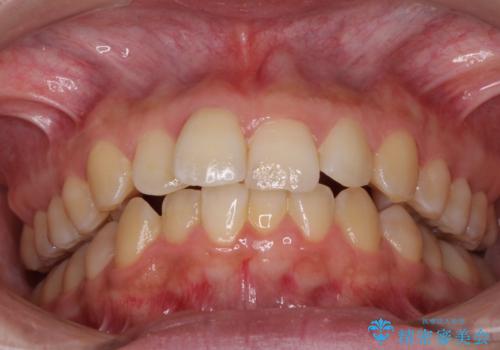

前歯のデコボコをインビザライン矯正で綺麗に改善

- 上下前歯のデコボコを気にして来院された患者様です。

全体的に叢生は軽度であったため、インビザラインにて矯正治療を行うこととしました。

舌の突出癖改善がうまくいかず、途中で舌小帯の切除を行いました。

気になる段差を納得いくまで改善させたため、治療期間は長くなりましたが、綺麗な仕上がりとなりました。